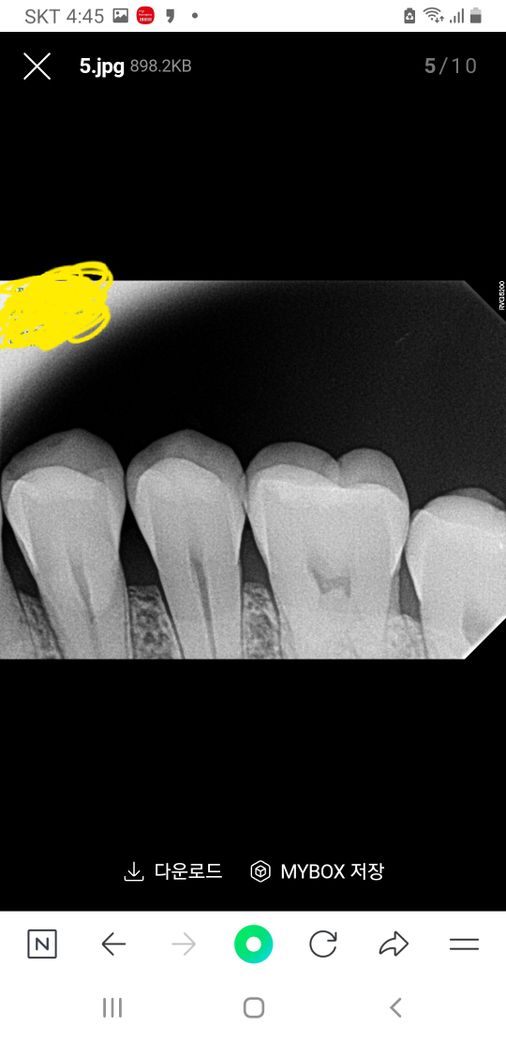

치근단사진좀 살펴봐 주세요. (치식과 충치여부)

치아 치근단사진 에서 보이는 치아가 몇번 (치식)

인지요? 충치나 파절이 있는지 궁금합니다.

겉으로는 검은색이 보이는데 오른쪽 위 뒤에서 세번째.

치근단사진상 보이는 것이 있는지요?

엑스레이 상으로는 치아 사이는 크게 충치가 잇어 보이진 않습니다. 사진에서 보이는 큰 어금니의 씹는면은 약간 깨진부위가 잇는거 같습니다.

교익 사진으로만 봤을 경우에는 큰 충치가 보이지는 않습니다.

하지만 육안상으로 보이는 충치가 있을 수 있기 때문에 정확한 확인을 위해서는 치과에서 진료를 받아 보는 것이 좋습니다.

25번 치아이고 방사선사진상 충치나 파절은 보이지 않습니다

육안으로 보이는 검은색 선은 초기충치일 가능성이 있습니다